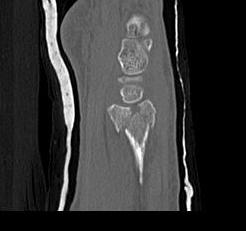

Distal Radius Fracture Articular Step Coronal CTDistal Radius Fracture Articular Step Sagittal CT

Distal Radius Fracture DRUJ incongruentDRUJ FractureDRUJ Fracture CT

Sigmoid notch disruption and DRUJ instability